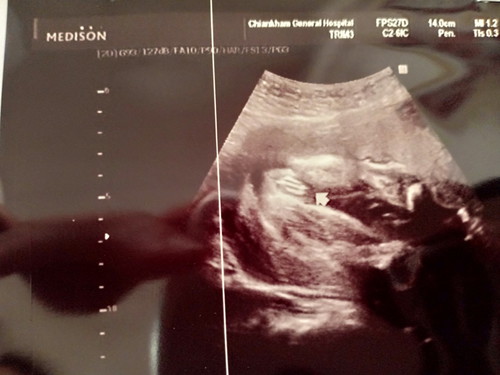

แบบนี้ผู้หญิง100%ไหมคะ

หมอบอกผู้หญิง... แต่คนที่บ้านบอกอาจเป็นผู้ชายหนีบไว้ แม่ๆช่วยดูให้หน่อยคะว่า ญ ช

ญ ค่ะ ชัดมากเลยได้ลูกสาวแล้วคุณแม่ดีใจด้วยนะคะ